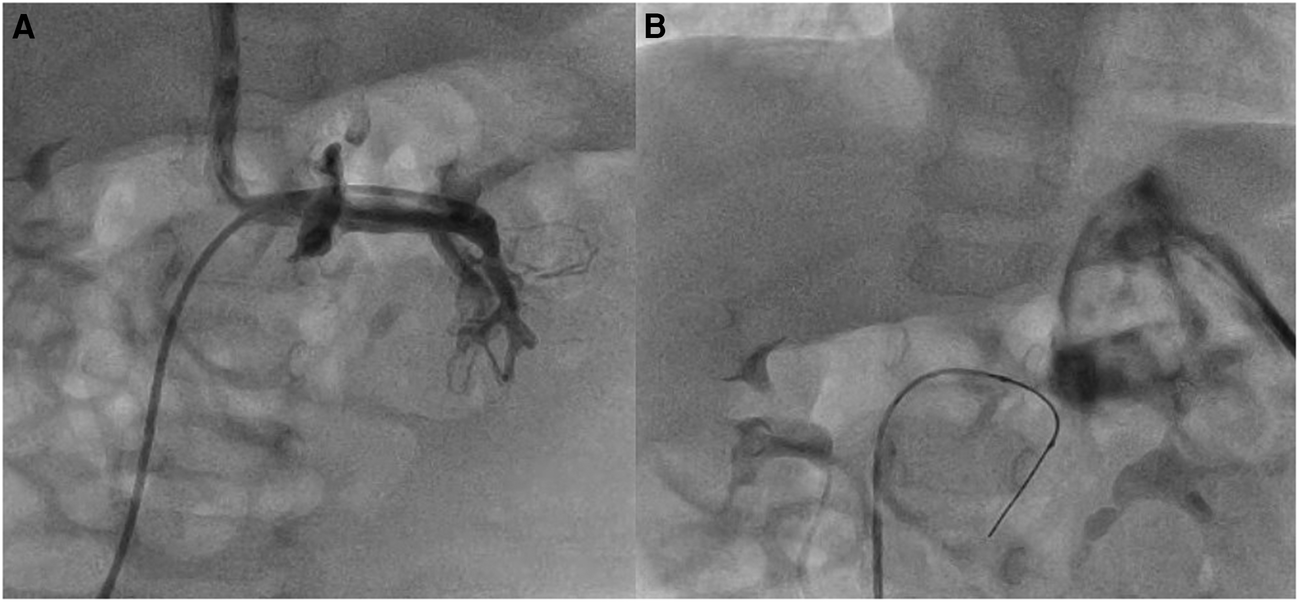

In three patients with severe aortic valve stenosis (no. 4, no. 6, and no. 8), the plane of the aortic valve root was more vertically oriented, with a large right cusp and short left cusp. The use of SwiftNINJA gave us the right angulation of the catheter tip to orient the coronary wire in the right direction and easily cross the valve (Figure 3). In patient no. 17 with Damus-Kaye-Stansel repair, we used the SwiftNINJA to cross an apical trabeculated ventricular septal defect, create an arterio-venous circuit and close the defect from the jugular vein (Supplementary Video S1).

FIGURE 3

www.frontiersin.org

Figure 3. Baseline aortic root angiogram (A,B). SwiftNINJA is articulated perpendicular to the plane of the aortic valve root (to the left and posteriorly) to orient the coronary wire in the right direction and cross easily the valve (C,D).